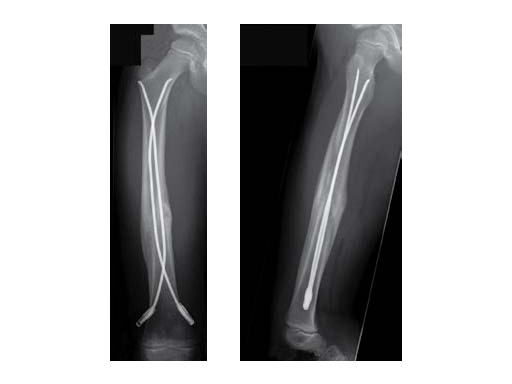

6-year-old girl, ski injury.

X-rays show a long spiral fracture of the proximal third of the right femur (32D/5.1). Because of the age good indication for ESIN, but some danger of instability is possible.

cd

Postoperative x-rays. A closed reduction and fixation with 3.0 mm TEN was carried out with correct child-oriented alignment. For stability reasons two End Caps became uses. No signs of a shortening can be seen.

ef

AP and lateral view 6 weeks after surgery shows good callus formation and still a perfect alignment.

Full weight bearing was then allowed.